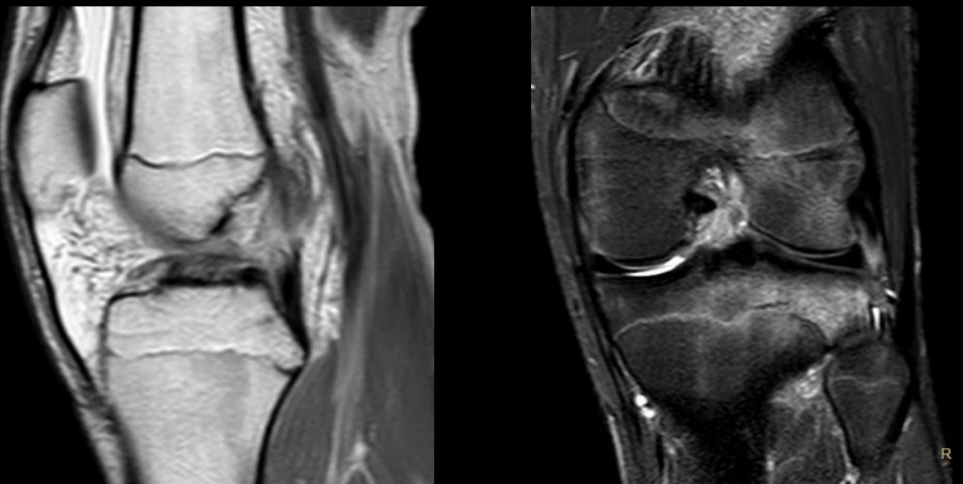

Cuál es el mejor estudio para ver un desgarro meniscal y qué permite ver?

RM

- Permite ver y caracterizar desgarros en múltiples planos